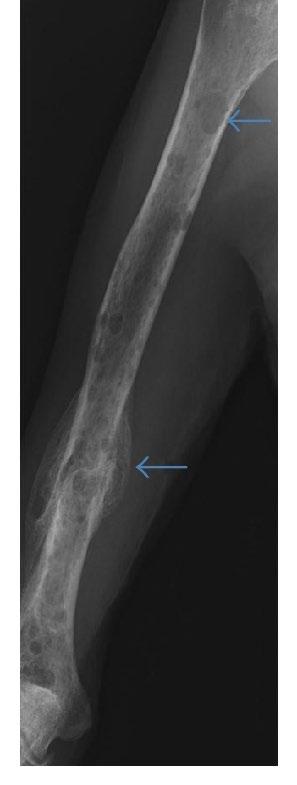

Conventional X-rays reveal punched-out lytic lesions, osteoporosis, or fractures in 75% of patients.

FDG PET/CT appears to be more sensitive (85%) than skeletal survey for the detection of small lytic bone lesions.